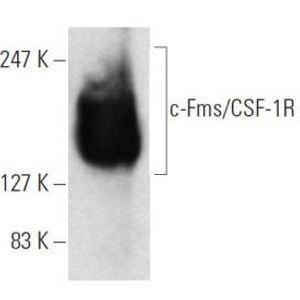

JAN 11, 2021ImmunologyMacrophages are a type of immune cell that can detect and destruct bacteria, viruses, and harmful materials. They a ...